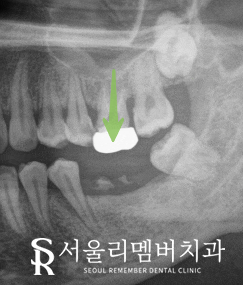

계획

간단하게 정리하면 비어 있는 곳은 임플란트로

주변에 있는 정출되고 기우러 아픈 치아들은

신경치료를 해주기로 했습니다.

꼼꼼한 진행

수면마취를 진행하고

식립을 진행하는데요.

잠을 자는듯한 진정된 상태에서

저희 의료진은 환자 모니터링 장비를 사용해

더 안전한 환경에서 식립을 완료했습니다.

그리고 신경치료까지 마무리했는데요.